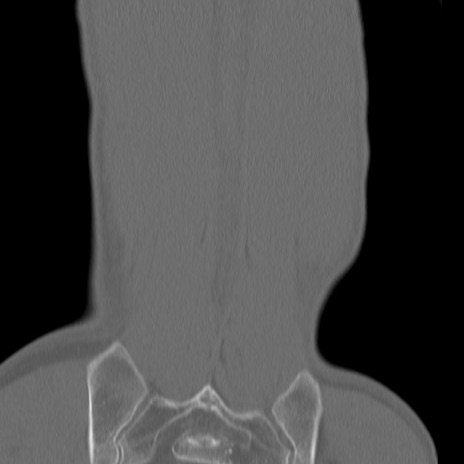

腰椎CT

矢状断像